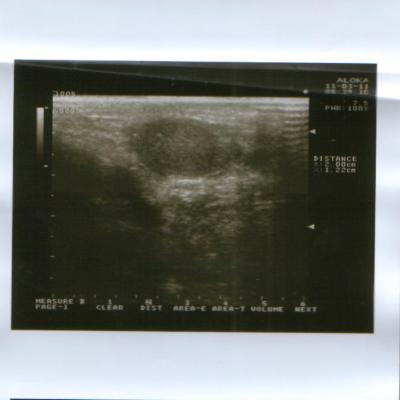

Сегодня(11.03.2011 г.)я ходил на приём к урологу.После осмотра он направил меня на УЗИ мошонки,простаты,мочевого пузыря и почек.УЗИ мошонки показало,что левое яичко действительно сжалось и почти в три раза меньше правого.Уролог сказал,что скорее всего,летняя операция грыжесечения и нынешняя проблема связаны и поставил мне диагноз "Атрофия левого яичка".А,да.УЗИ остальных органов показали,что всё остальное в порядке.Туберкулёза у меня не было и контактов с больными им тоже не было.

Снимки УЗИ и заключение уролога в прикреплённом архиве